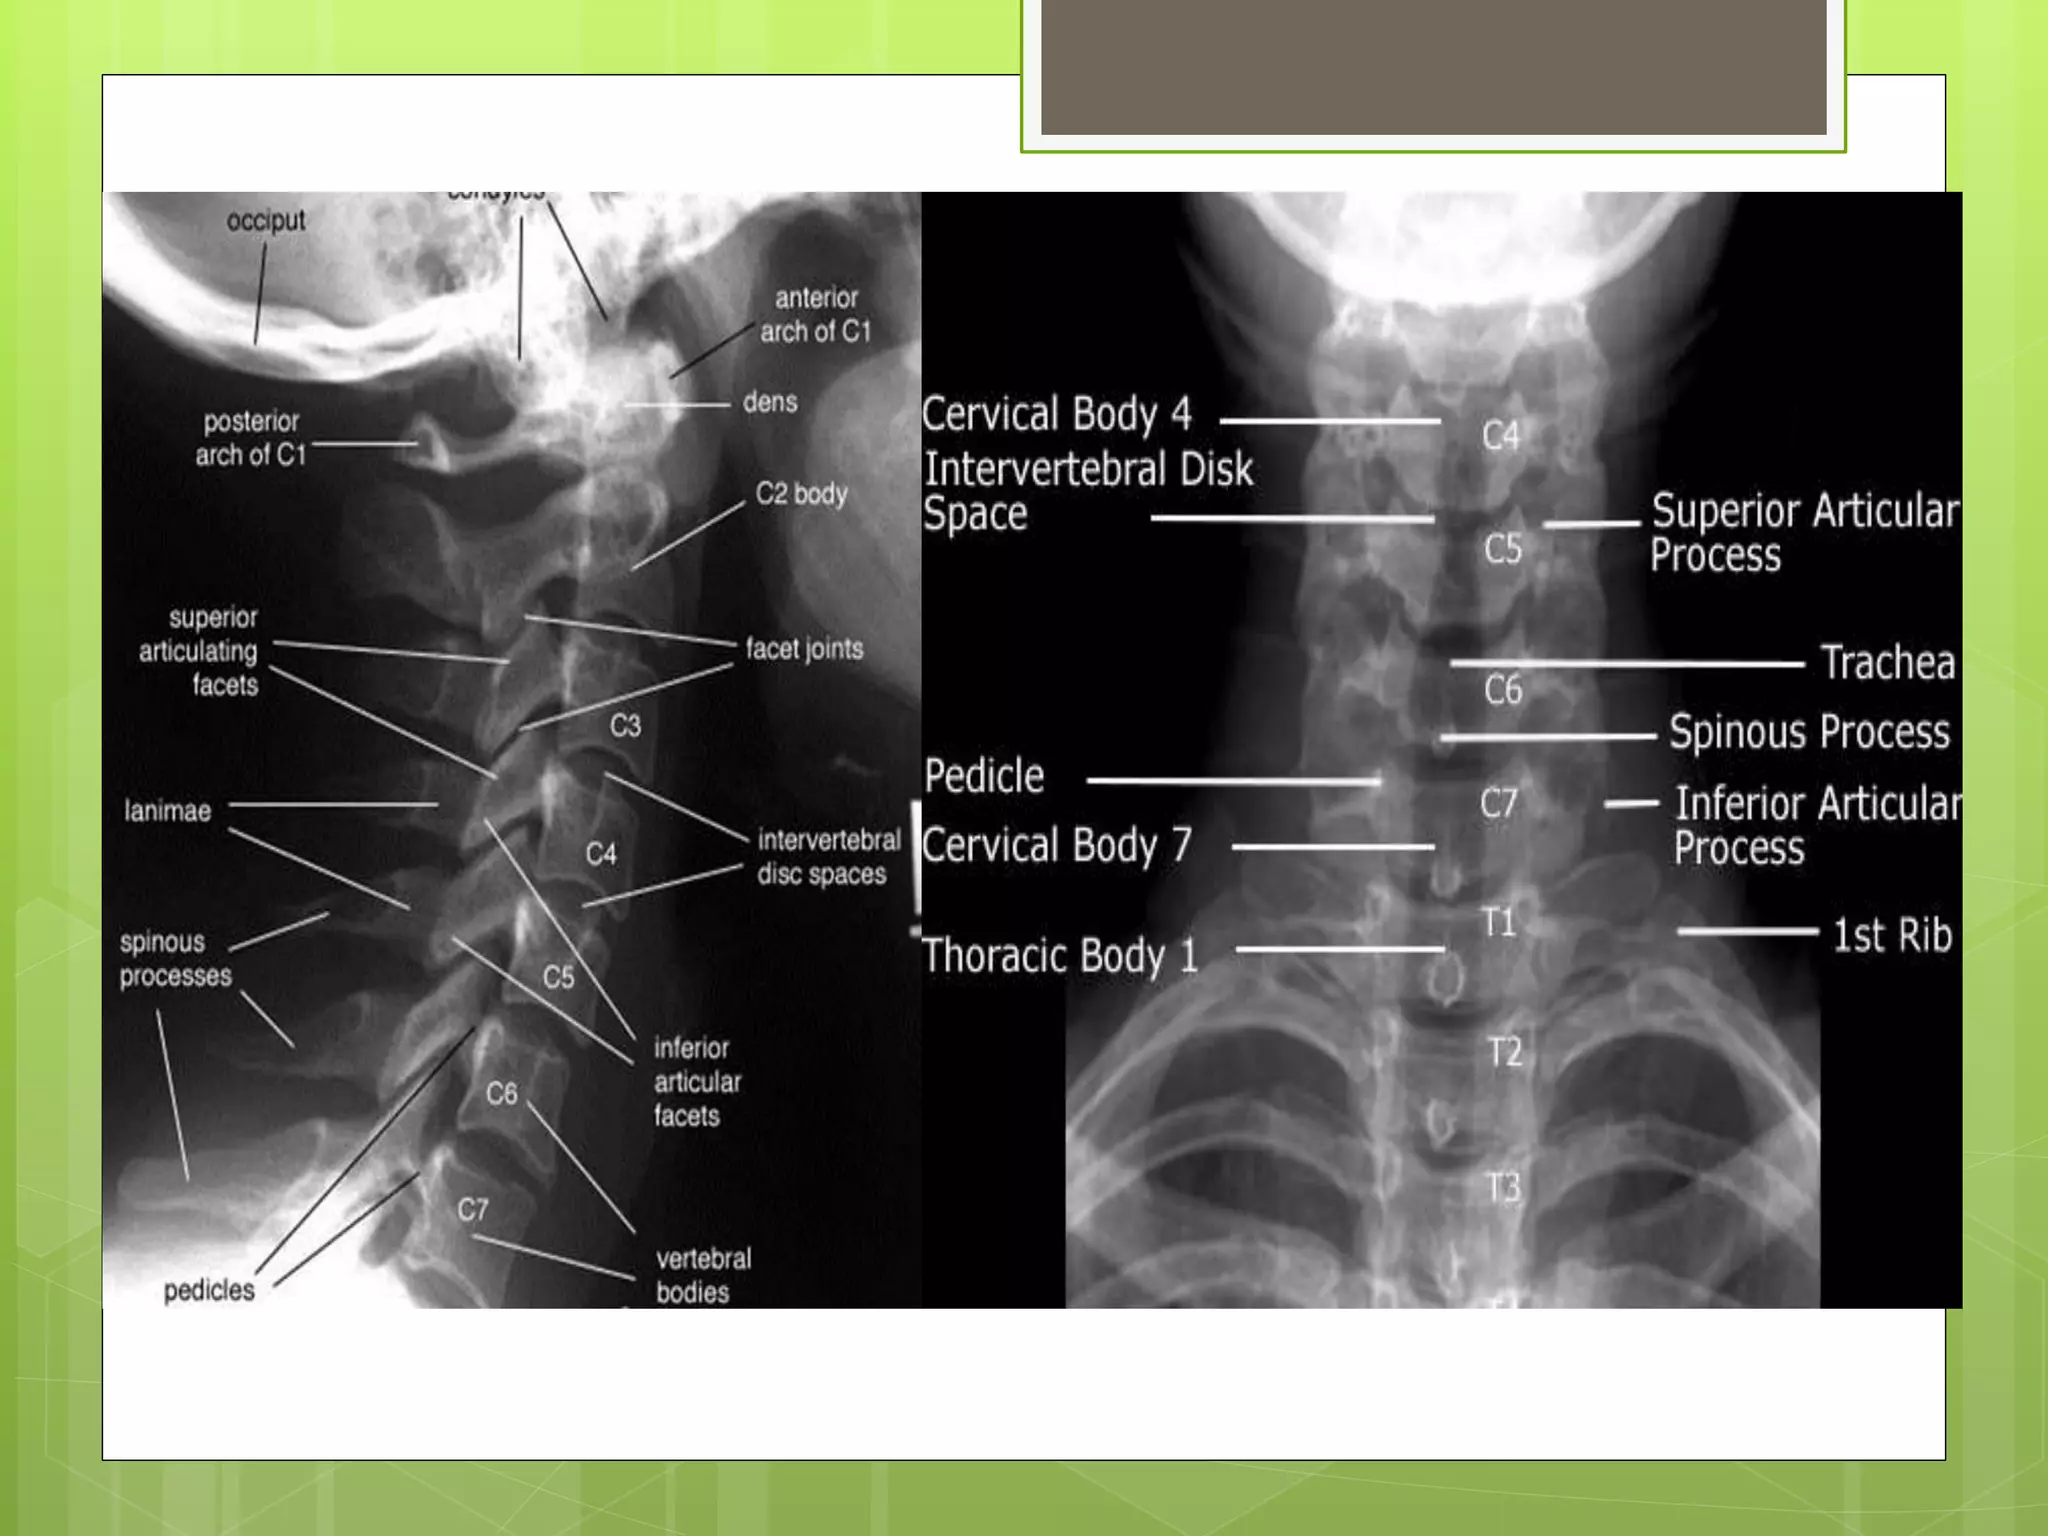

INVESTIGATIONS

 1) X Rays

Antero-posterior view

Lateral view

Open mouth view for dens

 Stress X-Rays (neutral,flexion,extention)

 Tomogram (rare) hypoplastic odontoid,

occipitalisation of atlas are clearly visualised.